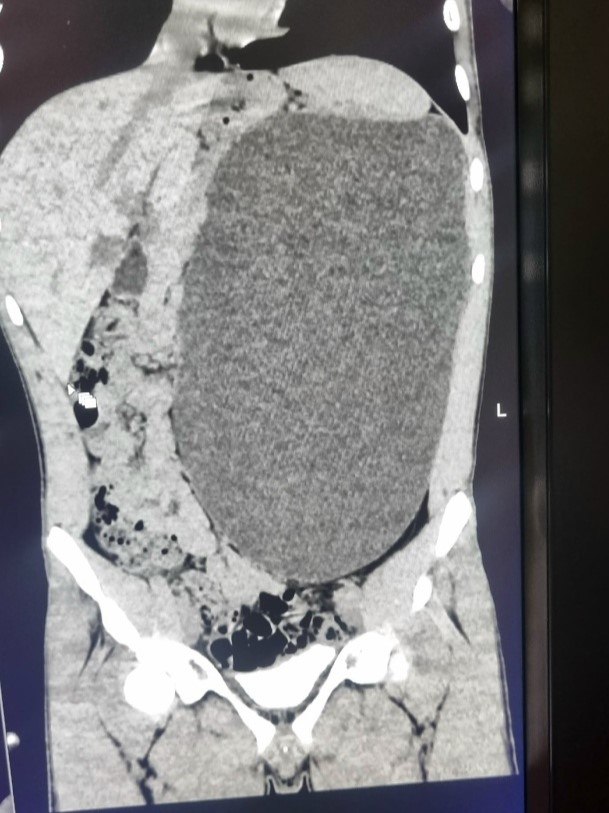

Гигантскую почку размером с пятилитровую бутылку удалили у 17-летнего подростка в Новосибирске.

Орган занимал почти весь объем живота и мог разорваться в любой момент, сообщили в Минздраве области.

Патологию выявили случайно при медосмотре перед устройством юноши на работу. До обследования он не испытывал никаких симптомов и считал себя полностью здоровым.

Фото: Минздрав Новосибирской области